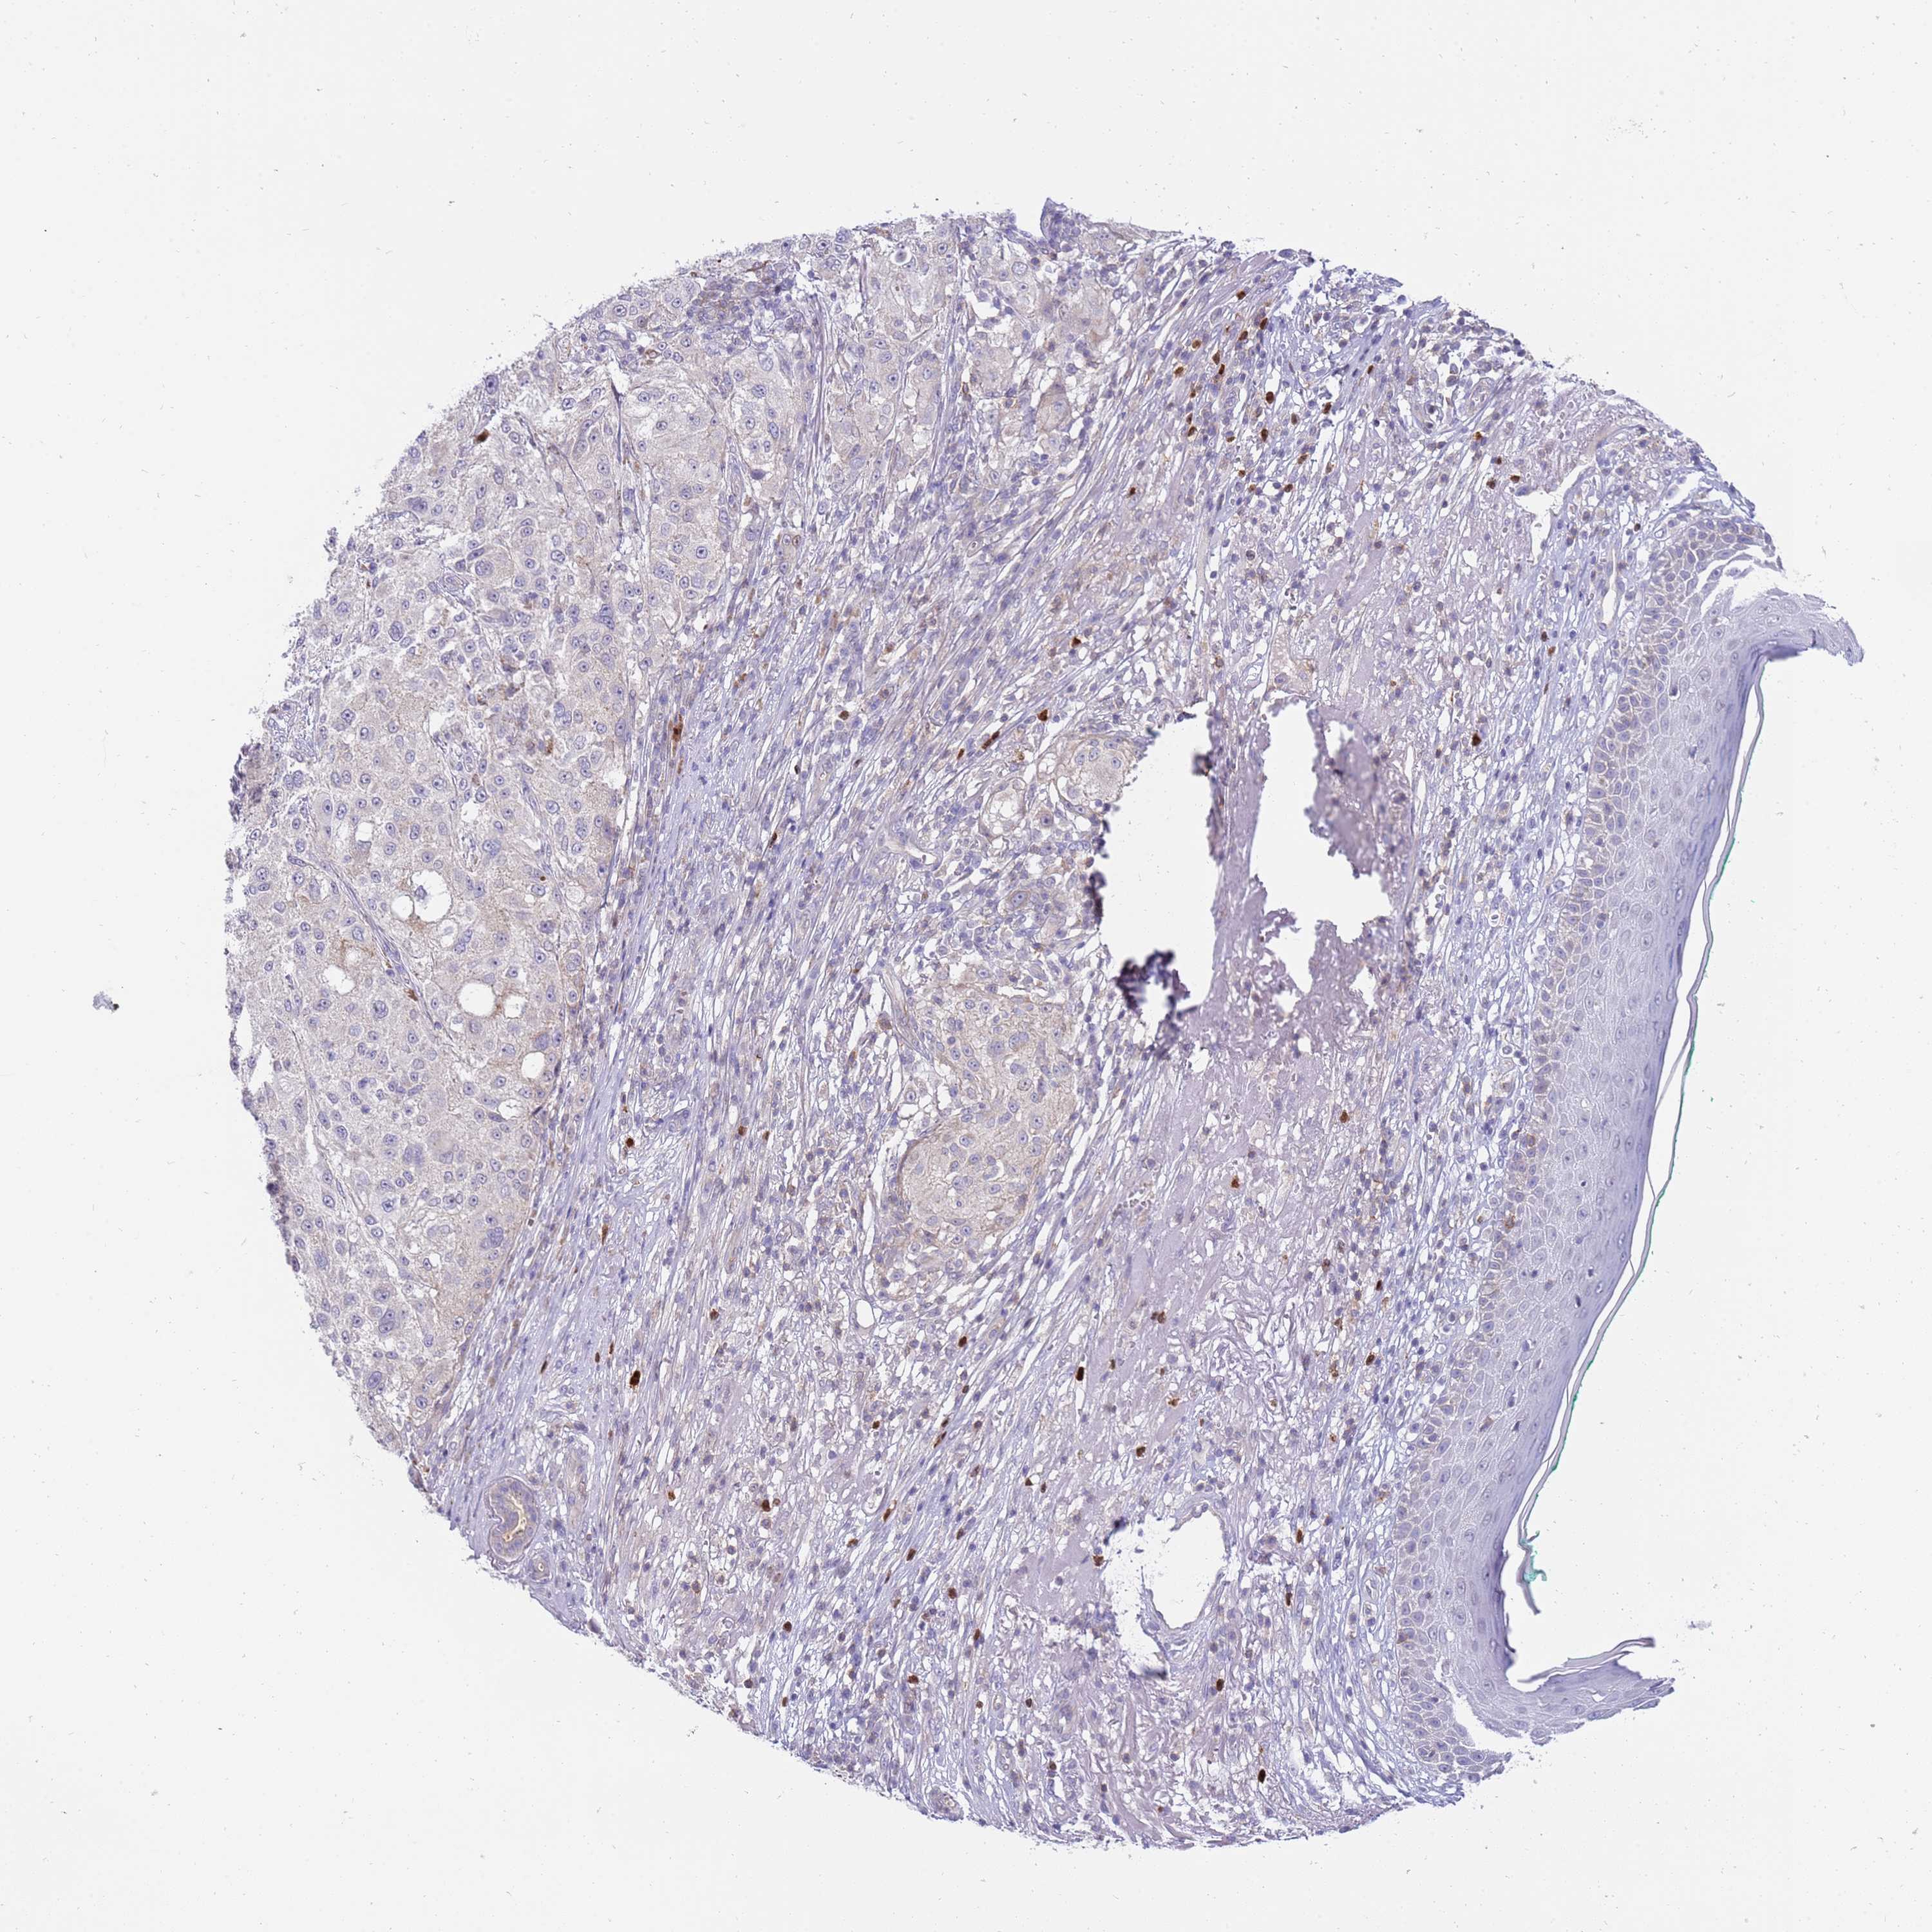

MELANOMA - Protein expressioni

A mouse-over function shows sample information and annotation data. Click on an image to view it in a full screen mode. Samples can be filtered based on level of antibody staining by selecting one or several of the following categories: high, medium, low and not detected. The assay and annotation is described here.

Note that samples used for immunohistochemistry by the Human Protein Atlas do not correspond to samples in the TCGA dataset.

Antibody stainingi

Antibody staining in the annotated cell types in the current human tissue is reported as not detected, low, medium, or high, based on conventional immunohistochemistry profiling in selected tissues. This score is based on the combination of the staining intensity and fraction of stained cells.

Each image is clickable and will lead to virtual microscopy that enables deeper exploration of all samples and also displays staining intensity scores, fraction scores and subcellular localization as well as patient and tissue information for each sample.

Antibody HPA047147

Staining

High

Medium

Low

Not detected

Intensity

Strong

Moderate

Weak

Negative

Quantity

>75%

75%-25%

<25%

None

Location

Nuclear

Cytoplasmic/membranous

Cytoplasmic/membranous,nuclear

Malignant melanoma, NOS

Malignant melanoma, Metastatic site